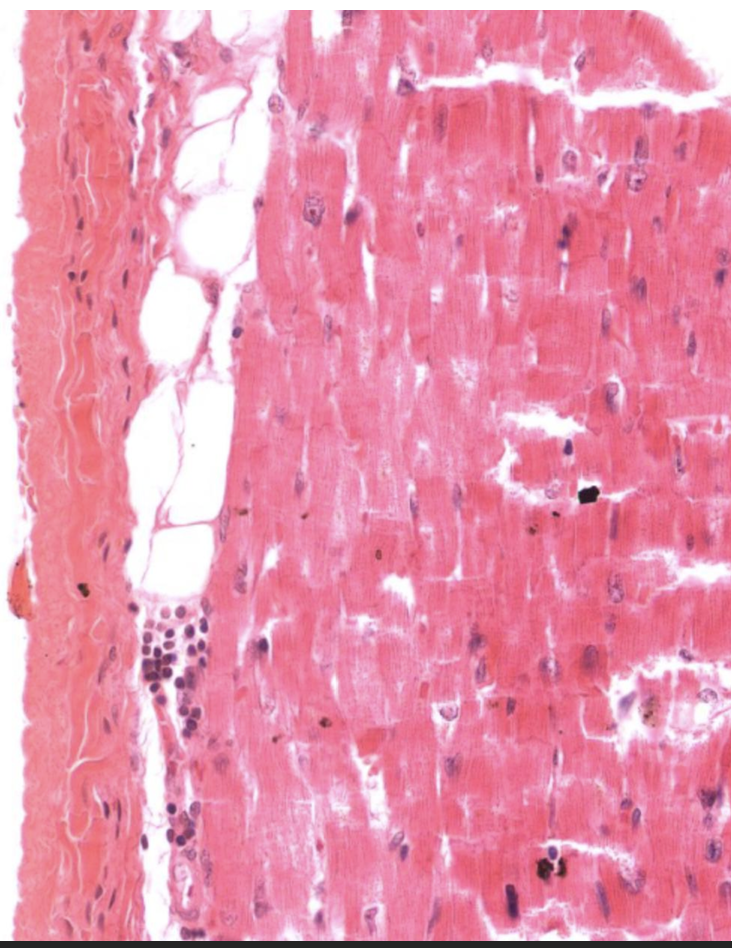

Identify Which partition this is and Where?

I = Myocardium in Ventricle.

(Char = Cardiac M. Is the thickest layer v/ ventricular folds called trabecular carnae)